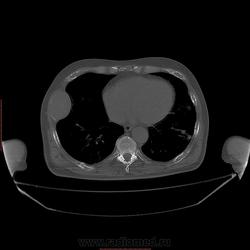

Пациент 1946 г.р., состоит на Д учете в онкодиспансере по поводу с-ч кожи (базалиома), прошел курс лучевой терапии, в 2009г на Ргенографии выявили образование 7 ребра, направили на Кт, на КТ (2009г) был выставлен д-з ГКО, пункционная биопсия не произведена. А сейчас вот такая картина, с множественными литическими очагами в костях грудного склета + образование 7 ребра, с отрицательной динамикой.

повторно взяли пациента, сняли кости таза, такая же картина- множественные очаги литической деструкции. Заключение: больше данных за миеломную болезнь.